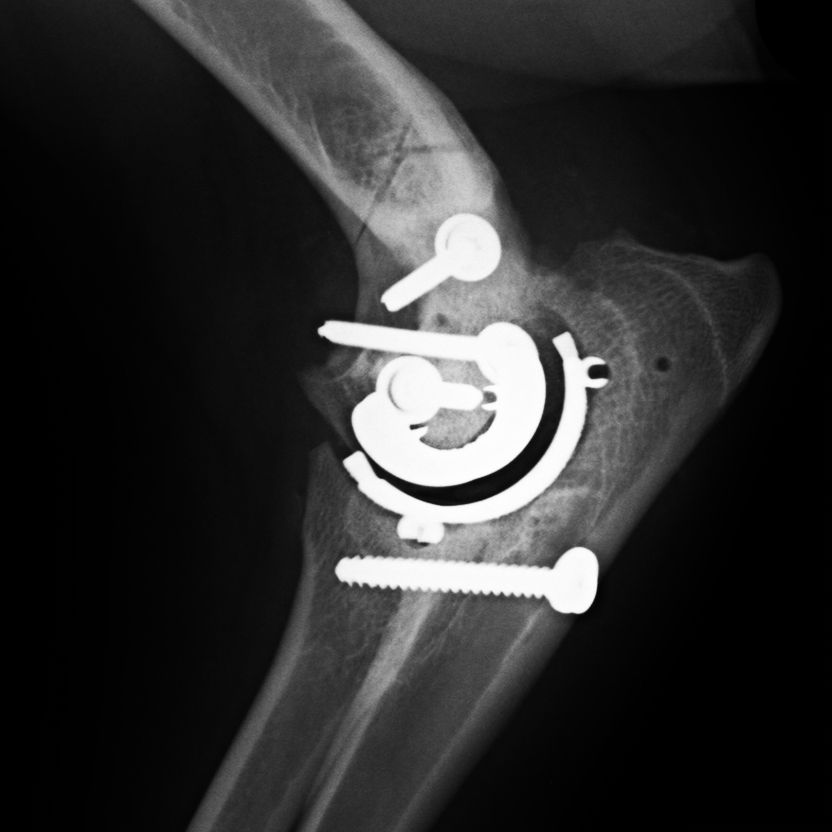

Joint Replacement Society

- Public education regarding joint replacement options, procedures, and outcomes

- Clinician support and resources for surgeons developing joint replacement programs